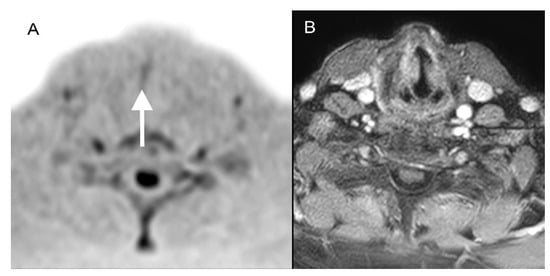

3.2. Findings of Standard MRI

3.3. Findings of DWIBS

3.4. Findings of Standard MRI + DWIBS